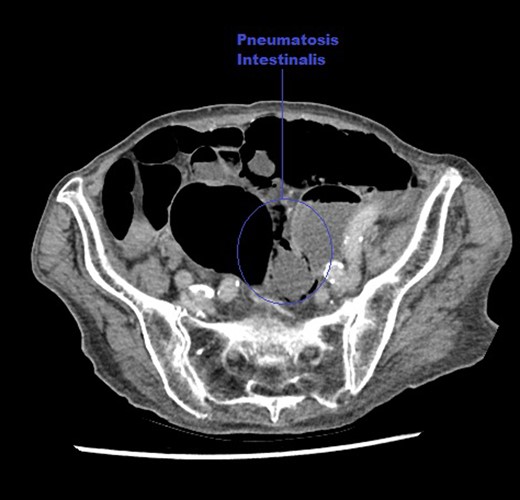

An axial CT image of the abdomen taken at initial presentation, demonstrating PI marked on the image.

An axial CT image of the pelvis in lung view windows, taken at initial presentation clearly demonstrating intra-mural air within the bowel, marked on image.